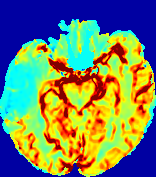

LesionRefer to captionRefer to captionRefer to captionRefer to captionRefer to captionRefer to caption𝐕rgbsubscript𝐕𝑟𝑔𝑏{\bf{V}}_{rgb}Refer to captionRefer to captionRefer to captionRefer to captionRefer to captionRefer to caption𝐕2subscriptnorm𝐕2{\|\bf{V}}\|_{2}Refer to captionRefer to captionRefer to captionRefer to captionRefer to captionRefer to captionRefer to caption3.53.53.52.82.82.82.12.12.11.41.41.40.70.70.70.00.00.0(mm/s)𝑚𝑚𝑠(mm/s)D𝐷DRefer to captionRefer to captionRefer to captionRefer to captionRefer to captionRefer to captionRefer to caption0.0200.0200.0200.0160.0160.0160.0120.0120.0120.0080.0080.0080.0040.0040.0040.0000.0000.000(mm2/s)𝑚superscript𝑚2𝑠(mm^{2}/s)Slice #1Slice #2Slice #3Slice #4Slice #5Slice #6

Figure 3: PIANO feature maps for one stroke patient, where the lesion is located in the left hemisphere. Top row: segmented stroke lesion region (white) on different slices, obtained from ISLES 2017. The corresponding slices for the PIANO feature maps are shown in the following rows.

For a better insight into an estimated velocity field 𝐕𝐕{\bf{V}} and diffusion field 𝐃𝐃{\bf{D}}, we compute the following maps: (1) 𝐕rgbsubscript𝐕𝑟𝑔𝑏{\bf{V}}_{rgb}: Color-coded orientation map of 𝐕=(Vx,Vy,Vz)T𝐕superscriptsuperscript𝑉𝑥superscript𝑉𝑦superscript𝑉𝑧𝑇{\bf{V}}=(V^{x},V^{y},V^{z})^{T}, obtained by normalizing 𝐕𝐕{\bf{V}} to unit length and mapping its 3 components to red, green, blue respectively; (2) 𝐕2subscriptnorm𝐕2\|{\bf{V}}\|_{2}: 222 norm of 𝐕𝐕{\bf{V}}; (3) D𝐷D: scalar field in Eq. 5.

Fig. 3 and Fig. 4 show the PIANO feature maps estimated from two ISLES 2017 patients: all are highly consistent with the lesion in both cases. Details of the blood flow trajectories are revealed in 𝐕rgbsubscript𝐕𝑟𝑔𝑏{\bf{V}}_{rgb} by the ridged patterns and the sharp changes of colors in the unaffected (right) hemisphere, while the flat patterns appearing within the lesion provide little directional information about the velocity and indicate low velocity magnitudes. Velocity magnitudes are more directly visualized via 𝐕2subscriptnorm𝐕2\|{\bf{V}}\|_{2}, from which one can easily locate the lesion where 𝐕2subscriptnorm𝐕2\|{\bf{V}}\|_{2} is low. D𝐷D also indicates lower diffusion values in the lesion, though with less contrast potentially due to the fact that it captures the accumulated effect of CA diffusion at the voxel-level.